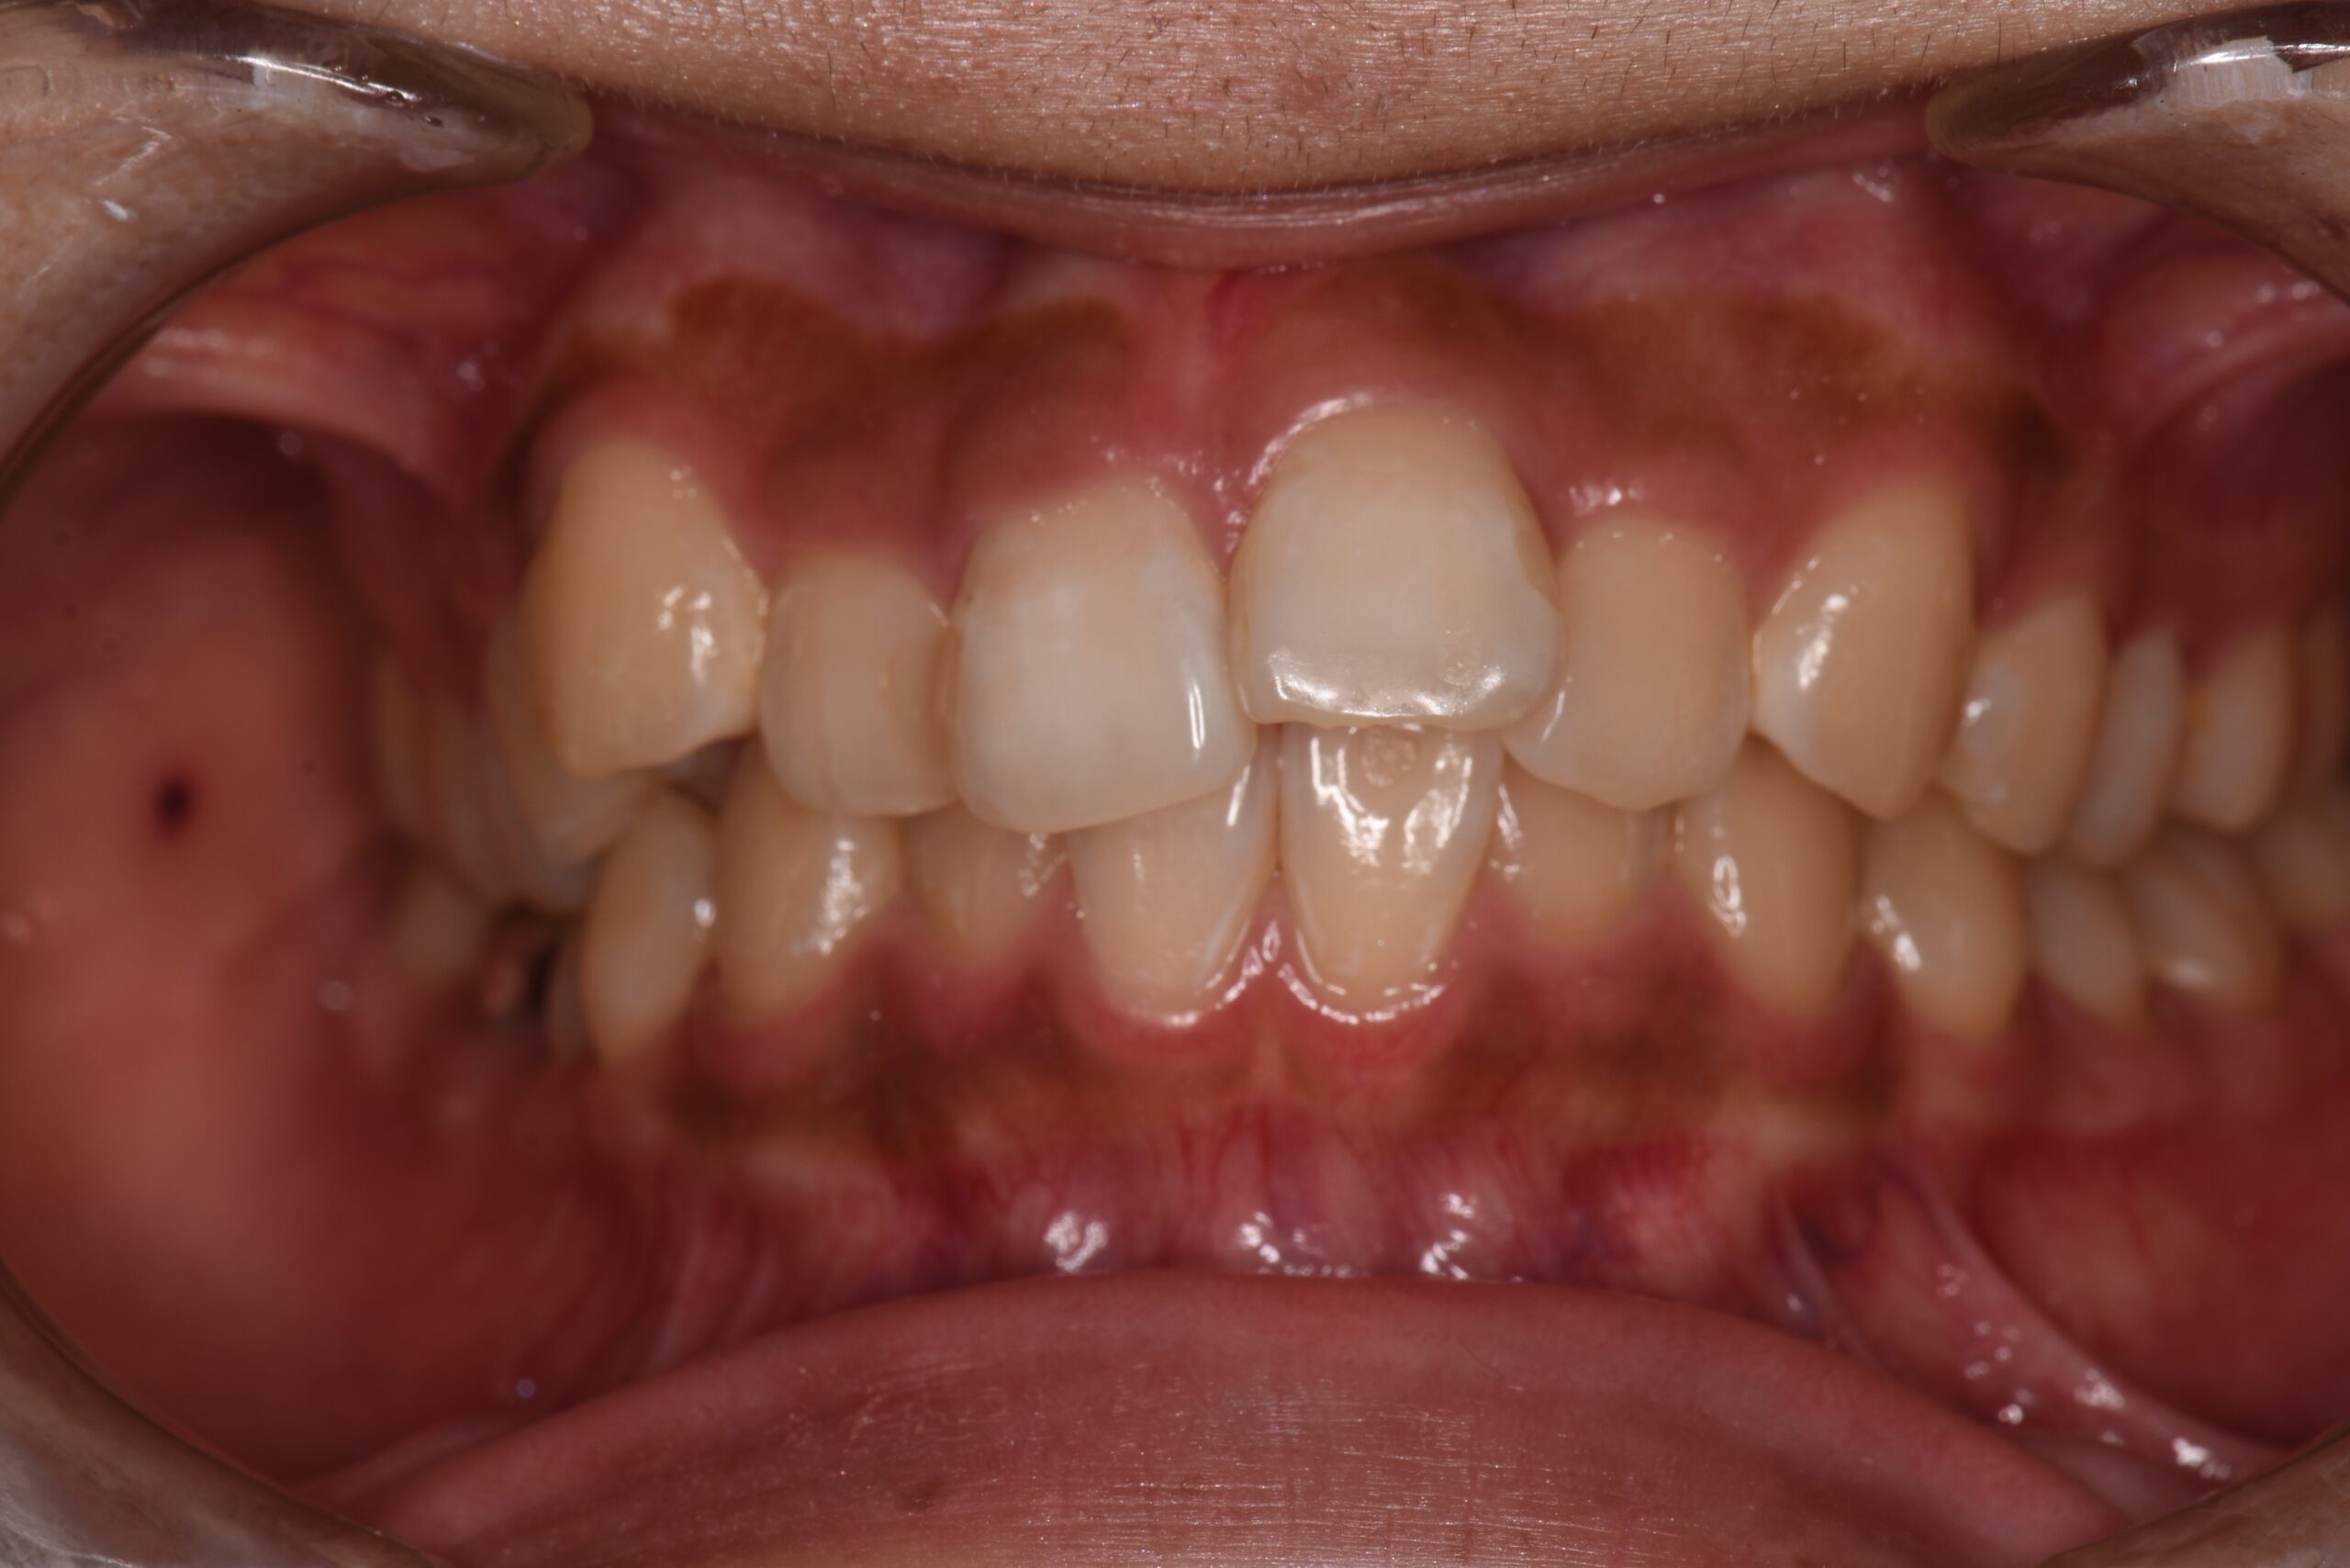

下の歯が上の歯よりも前に出ている状態です。

顎関節への負担や全身のバランスが悪くなる場合があり、お子様の場合は咀嚼が不十分になることで体の発育にも影響する可能性もあります。

よく噛むことは食べ物の消化のしやすさにも直結し、全身の健康にも影響します。

矯正治療で噛み合わせを整えることは、食事のしやすさの改善にも繋がります。